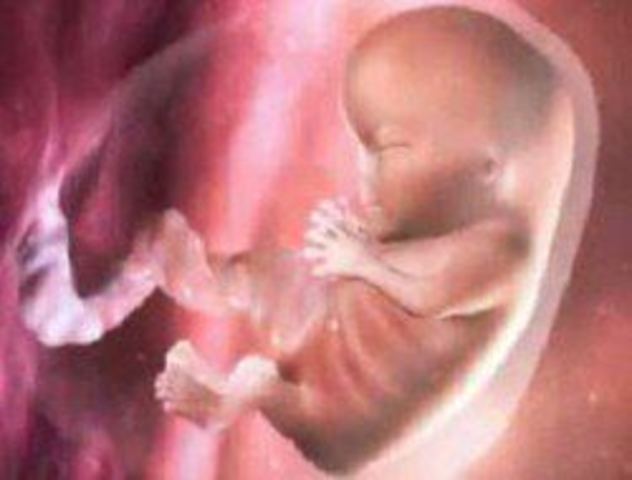

Alrededor de esta semana, el embrión se convierte en feto, en esta fase, los tejidos y órganos formados durante el periodo embrionario comienzan a madurar, el esqueleto comienza a tomar forma, al igual que el cordón umbilical comienza a ensancharse.

Su cabeza es demasiado grande en comparación de su cuerpo. Las fibras de los músculos así como los pulmones comienzan a desarrollarse.

Ya mide un centímetro y medio el embrión y comienza a rotar y doblar el cuerpo. Comienza el esbozo de las cuatro cavidades cardíacas y hay una formación incipiente de los dientes. Comienza el desarrollo de estómago, intestinos y sistema urinario.

en este punto, el embrión comienza a crecer un milímetro por día. Sus ojos se distinguen como dos puntos negros. Empiezan a desarrollarse las ampollas que se convertirán en sus extremidades.